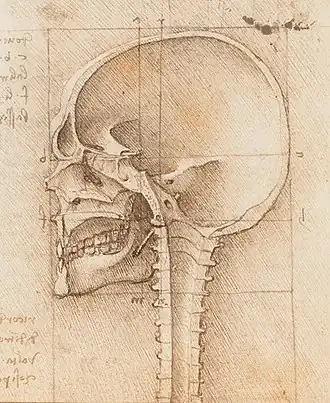

The term sagittal derives from the Latin word sagitta, meaning "arrow". An image of an arrow piercing a body and passing from front (anterior) to back (posterior) on a parabolic trajectory with the upright bow that shot it would be one way to demonstrate the derivation of the term. Another explanation would involve the notching of the sagittal suture posteriorly by the lambdoidal suture —similar to feathers on an arrow. The Oxford English Dictionary indicates that sagittal in the sense of the sagittal suture along the vertex of the skull pre-dates other anatomical usage.[7]